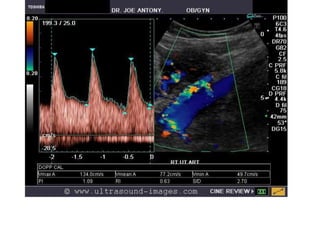

Color doppler and spectral waveform of the middle cerebral artery shows increased

diastolic flow in the brain suggesting a "fetal brain sparing" effect, whereby, the fetal

cerebral vessels "open up", lowering the cerebral vascular resistance to increase flow

to the brain thus diverting blood to the important organs in a state of overall hypoxia.